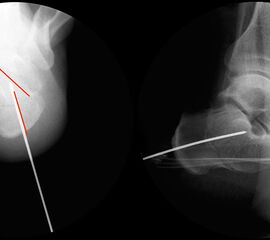

Bei Rückfussfehlstellungen ist meist eine knöcherne Korrektur des Kalkaneus indiziert. Dabei wird das Fersenbein im Bereich des Tuber calcanei durchtrennt und der Achillessehnenansatz nach medial oder lateral geschoben. Zusätzlich ist eine Rotation des Tuber möglich, wodurch sich der Korrektureffekt noch verstärkt. Durch die Wahl der Osteotomieebene kann die Verscheibung mit einer Verlängerung oder Verkürzung des Fersenbeins kombiniert werden. Die Osteosynthese erfolgt typischerweise durch perkutan eingebrachte Schrauben.

Durch eine V-förmige Schnittführung kann eine Translation des Tuber calcanei nach dorsal zuverlässig verhindert werden, bei hoher primärer Stabilität.

Operationsplanung anhand der Röntgenaufnahmen unter Beachtung wichtiger radiologischer Landmarks wie Rückfussachse, Metatarsale I – Talushals-Achse im dp und lateralen Strahlengang (Abbildung 1 und 2).

Abbildung 2